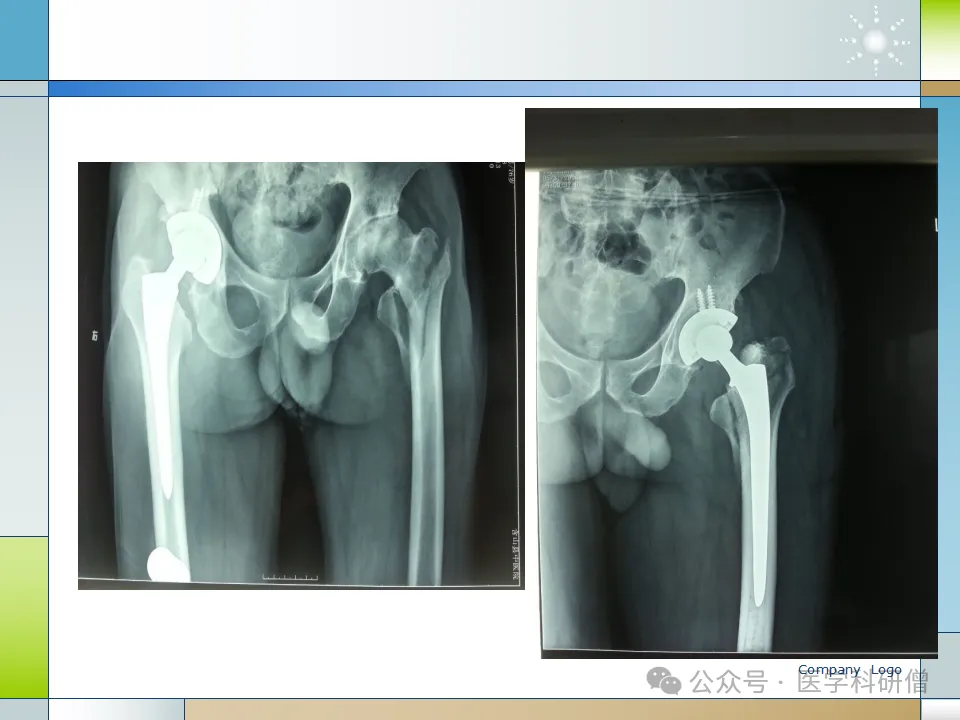

6. 人工关节置换

对于高龄、粉碎性骨折、骨质疏松等严重情况的患者,人工关节置换可能是一种更好的选择。人工关节置换能够迅速恢复患者的活动能力,避免长期卧床导致的并发症。然而,关节置换手术风险较高,对医生的技术和经验要求较高。